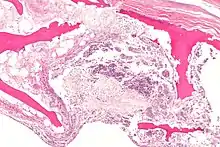

ANFH can only be diagnosed by MRI of the hip and X-rays of the hip specifically in the anteroposterior and frog-leg lateral poses.[2] Along with these scans an additional bone scan needs to be done which allows doctors to see the activities of bone cells in a body. Once the images that the physician want are obtained, they are then measured through two systematic reviews.